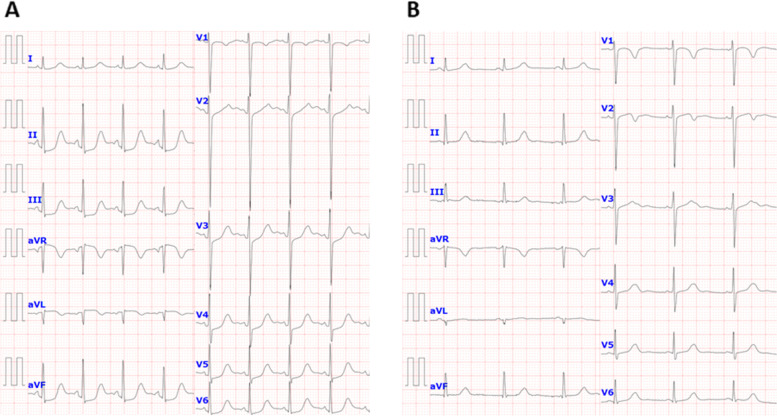

Five days after onset, brain MRI showed regions of hyperintensity in the right frontal lobe, bilateral parietal cortex and subcortex, and bilateral cerebellar lobes on FLAIR images (Fig. 1A). In addition, although the apparent diffusion coefficient (ADC) map showed elevations (Fig. 1B), no region of hyperintensity was observed on the diffusion-weighted image (DWI), suggesting angioedema (Fig. 1C). No abnormal findings were observed on brain magnetic resonance angiography (MRA) at the time of onset of the first headache (Fig. 2A). However, four days after the onset, multiple cerebrovascular spasms were observed, in which alternate contractions and dilations of several main arteries occurred (Fig. 2B). On the electrocardiogram (ECG) five days after the onset of the first headache, ST depression was observed in limb leads II, III, and aVF, and in the chest leads V3 to V6 (Fig. 3A). Ultrasound cardiography (UCG) showed a hypokinesis at the base of the side of intraventricular septum, with a slight decrease in ejection fraction (EF = 51.6%) and in fractional shortening (FS = 25.9%) (Fig. 4A). Although no symptoms of angina were observed 5 days after onset of first headache, left ventricular hypofunction leading to impending heart failure was suspected. Therefore, a calcium channel blocker and a nitrate were administered.

Based on her clinical course and imaging findings, she was diagnosed with reversible cerebral vasoconstriction syndrome (RCVS) with cardiac involvement. We administered 5 mg of the calcium channel blocker amlodipine besylate, 25 mg of nitroglycerin, and 500 mg of the antiepileptic drug levetiracetam. The hyperintense regions on FLAIR images completely disappeared 23 days after onset of first headache. She showed no exacerbation of heart failure, and the ECG (Fig. 3B) and UCG (Fig. 4B) findings were found to be normal eight days after onset of first headache. To avoid the risk of vascular spasm by iodinated contrast medium, we did not perform cardiac catheterization or coronary computed tomography (CT)-angiography until her RCVS was fully controlled. Since no recurrence of symptoms was observed after the treatment, we performed coronary CT-angiography seven months after the onset, which showed no significant vasoconstriction in any coronary artery (Fig. 5A, B).

A notable feature of this case was that reversible cardiac involvement occurred concomitantly with RCVS. Despite the absence of chest symptoms, an increase in serum BNP levels, ST-T changes on ECG, and decreased EF and FS on UCG were seen and improved three days after therapy was started. This implies that there is cardiac involvement caused by Takotsubo cardiomyopathy or abnormalities in coronary arteries. So far, it has been reported that in a retrospective study 68 cases, from which 18 had patients had undergone UCGs around the period of active RCVS. Among them, three female patients who had no coronary artery disease or heart failure presented with wall motion abnormalities on UCG [ref. 9]. This report concluded that cardiac ventricular abnormalities may be a part of the RCVS spectrum. In another report, a middle-aged female patient with RCVS showed coronary artery spasm. The patient, with repetitive chest pain and transient wall-motion abnormalities on UCG, had experienced a thunderclap headache, and diffuse cerebral vasoconstriction was revealed on cerebral angiograms [ref. 10]; in this case, RCVS had developed after repeated coronary artery spasm. However, our case presented both cerebral and cardiac lesions almost coexisted. We did not perform the coronary angiography to avoid the adverse effect such as vasoconstriction by the contrast medium; however, coronary vasospasm may have occurred by the mechanism like that of cerebral vasospasm. Whilst, based on the UCG findings and ECG changes that cannot be explained by the distribution of coronary arteries, catecholamine cardiomyopathy such as reverse Takotsubo cardiomyopathy may have occurred by severe pain from thunderclap headache [ref. 11].